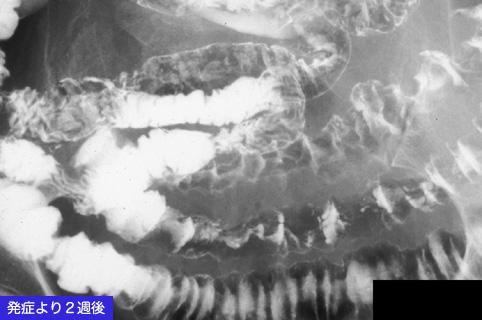

허혈성 소장염

류마티즘성 다발성 근통증에 발생한 허혈성 소장염

염증성 및 궤양성질환/허혈성 장염(혈전증 포함)

소장/회장

X-P